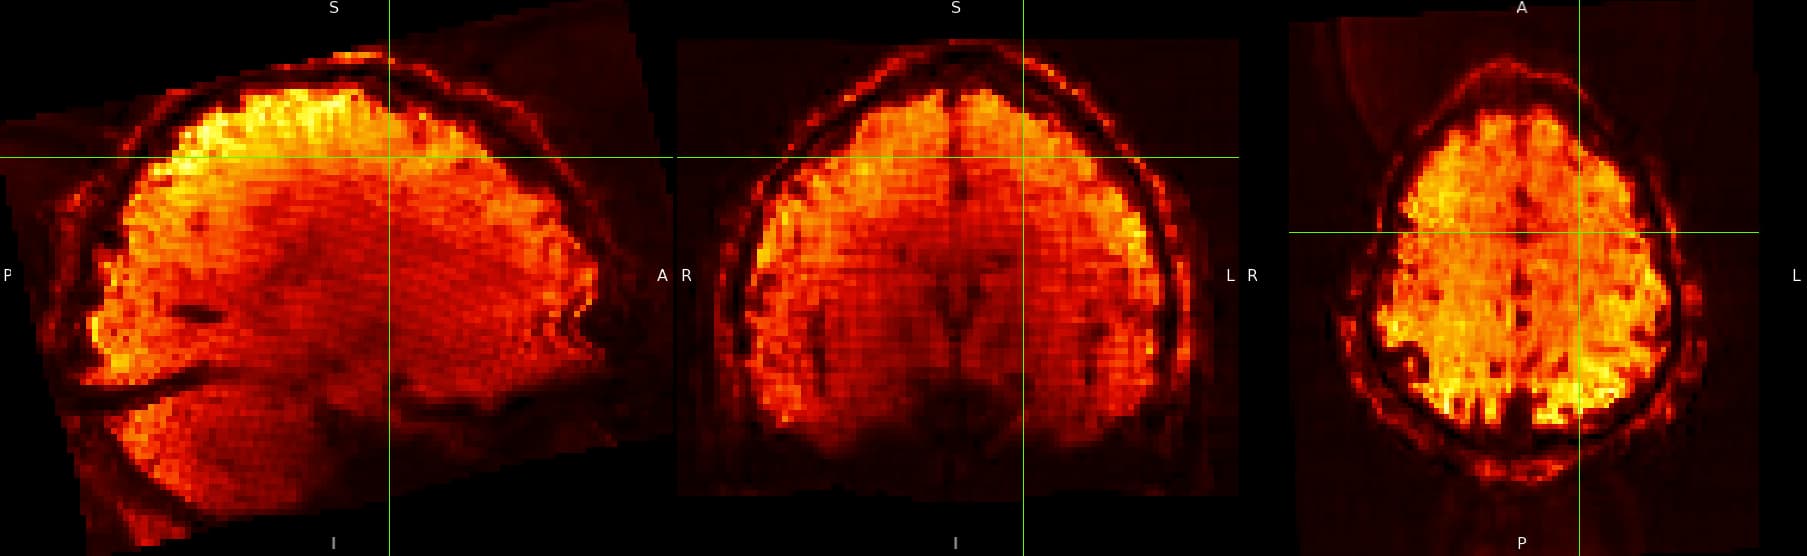

SE sequence in MNI152NLin6Asym-res1